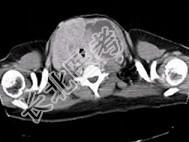

- 单项选择题青年女性,咽异物感1年, 环状软骨左下方触及一直径2厘米的光滑结节,随吞咽上下活动, 生长缓慢,颈部CT检查见下图, 患者诊断最可能为 ( )

C、甲状腺腺廇